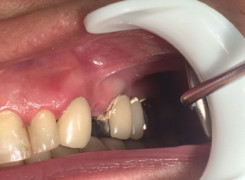

Pan Kamil zgłosił się do gabinetu po wypadku rowerowym w wyniku którego wybił ząb – lewą górną jedynkę. W takiej sytuacji została podjęta decyzja o implantacji natychmiastowej oraz zapatrzeniu pacjenta na czas integracji wszczepu w uzupełnienie tymczasowe.

Poniżej przebieg odbudowy protetycznej.